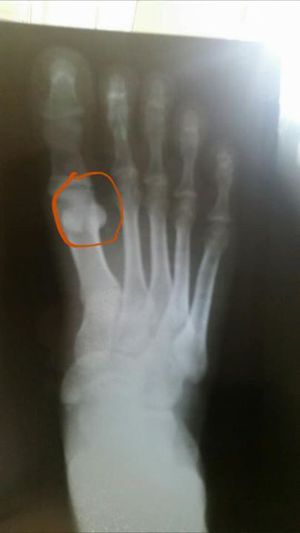

Dx??

Sesamoid bone?

There's an ostheophyt in the 1'th metatarsus bone?

Tuberculosis?

Ok that's better... rheumatoid arthritis?